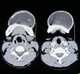

Cystic ameloblastoma

Ameloblastoma is a rare, benign tumor of odontogenic epithelium (ameloblasts, or outside portion, of the teeth during development) much more commonly appearing in the lower jaw than the upper jaw. It was recognized in 1827 by Cusack. [Source: Wikipedia ]